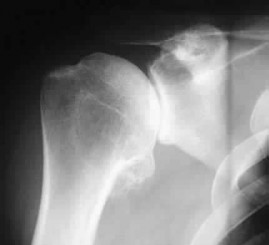

Question 81

A 65-year-old female sustains a 4-part proximal humerus fracture. Which of the following radiographic findings is the strongest predictor of ensuing humeral head ischemia according to Hertel criteria?

Explanation

According to Hertel et al., a metaphyseal calcar length of < 8 mm attached to the articular segment, a disrupted medial hinge, and a basicervical fracture pattern are the most accurate predictors of ischemia. Of these, a calcar length < 8 mm has the highest positive predictive value for avascular necrosis.